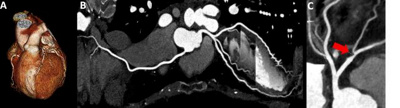

Darstellung des Herzens in 3D (A) sowie der Herzkranzgefässe in 2D (B). Nachweis einer höhergradigen, nicht verkalkten Verengung in einem der drei Hauptgefässe (roter Pfeil) (C).

Die Computertomographie (CT) des Herzens ist ein radiologisches Untersuchungsverfahren bei der Röntgenröhren und ein Detektorsystem um den Oberkörper kreisen und Schichtaufnahmen des Herzens erstellen. Diese erlaubt die Darstellung der Gefässe, die den Herzmuskel mit Blut versorgen (Herzkranzgefässe) sowie den Nachweis einer koronare Herzkrankheit (KHK) bei der es zu Verengungen (Stenosen) an den Gefässen kommt.

Die Herz CT hat sich gemäss internationalen Richtlinien bei Patienten mit einem niedrigen Risiko für eine KHK als exzellente Alternative zur invasiven Herzkatheteruntersuchung etabliert.